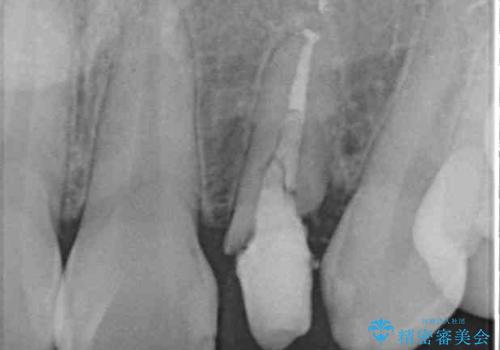

抜歯と言われた前歯 牽引してセラミッククラウンで保存する

- 他院で前歯の抜歯が必要と言われたとのことで来院された患者様です。

過去にぶつけたことで神経組織が壊死してしまったようで、その後むし歯が進行して歯肉深いところにまで進んでいる状態でした。

まずは部分矯正により歯を牽引し、歯肉や歯槽骨の位置を調整するために歯周外科処置を行い、治癒を待ってオールセラミッククラウンにて補綴治療を行うこととしました。

しっかりとむし歯を牽引したことで、クラウンの周りの腫れが引き、自然な口元に仕上げることができました。